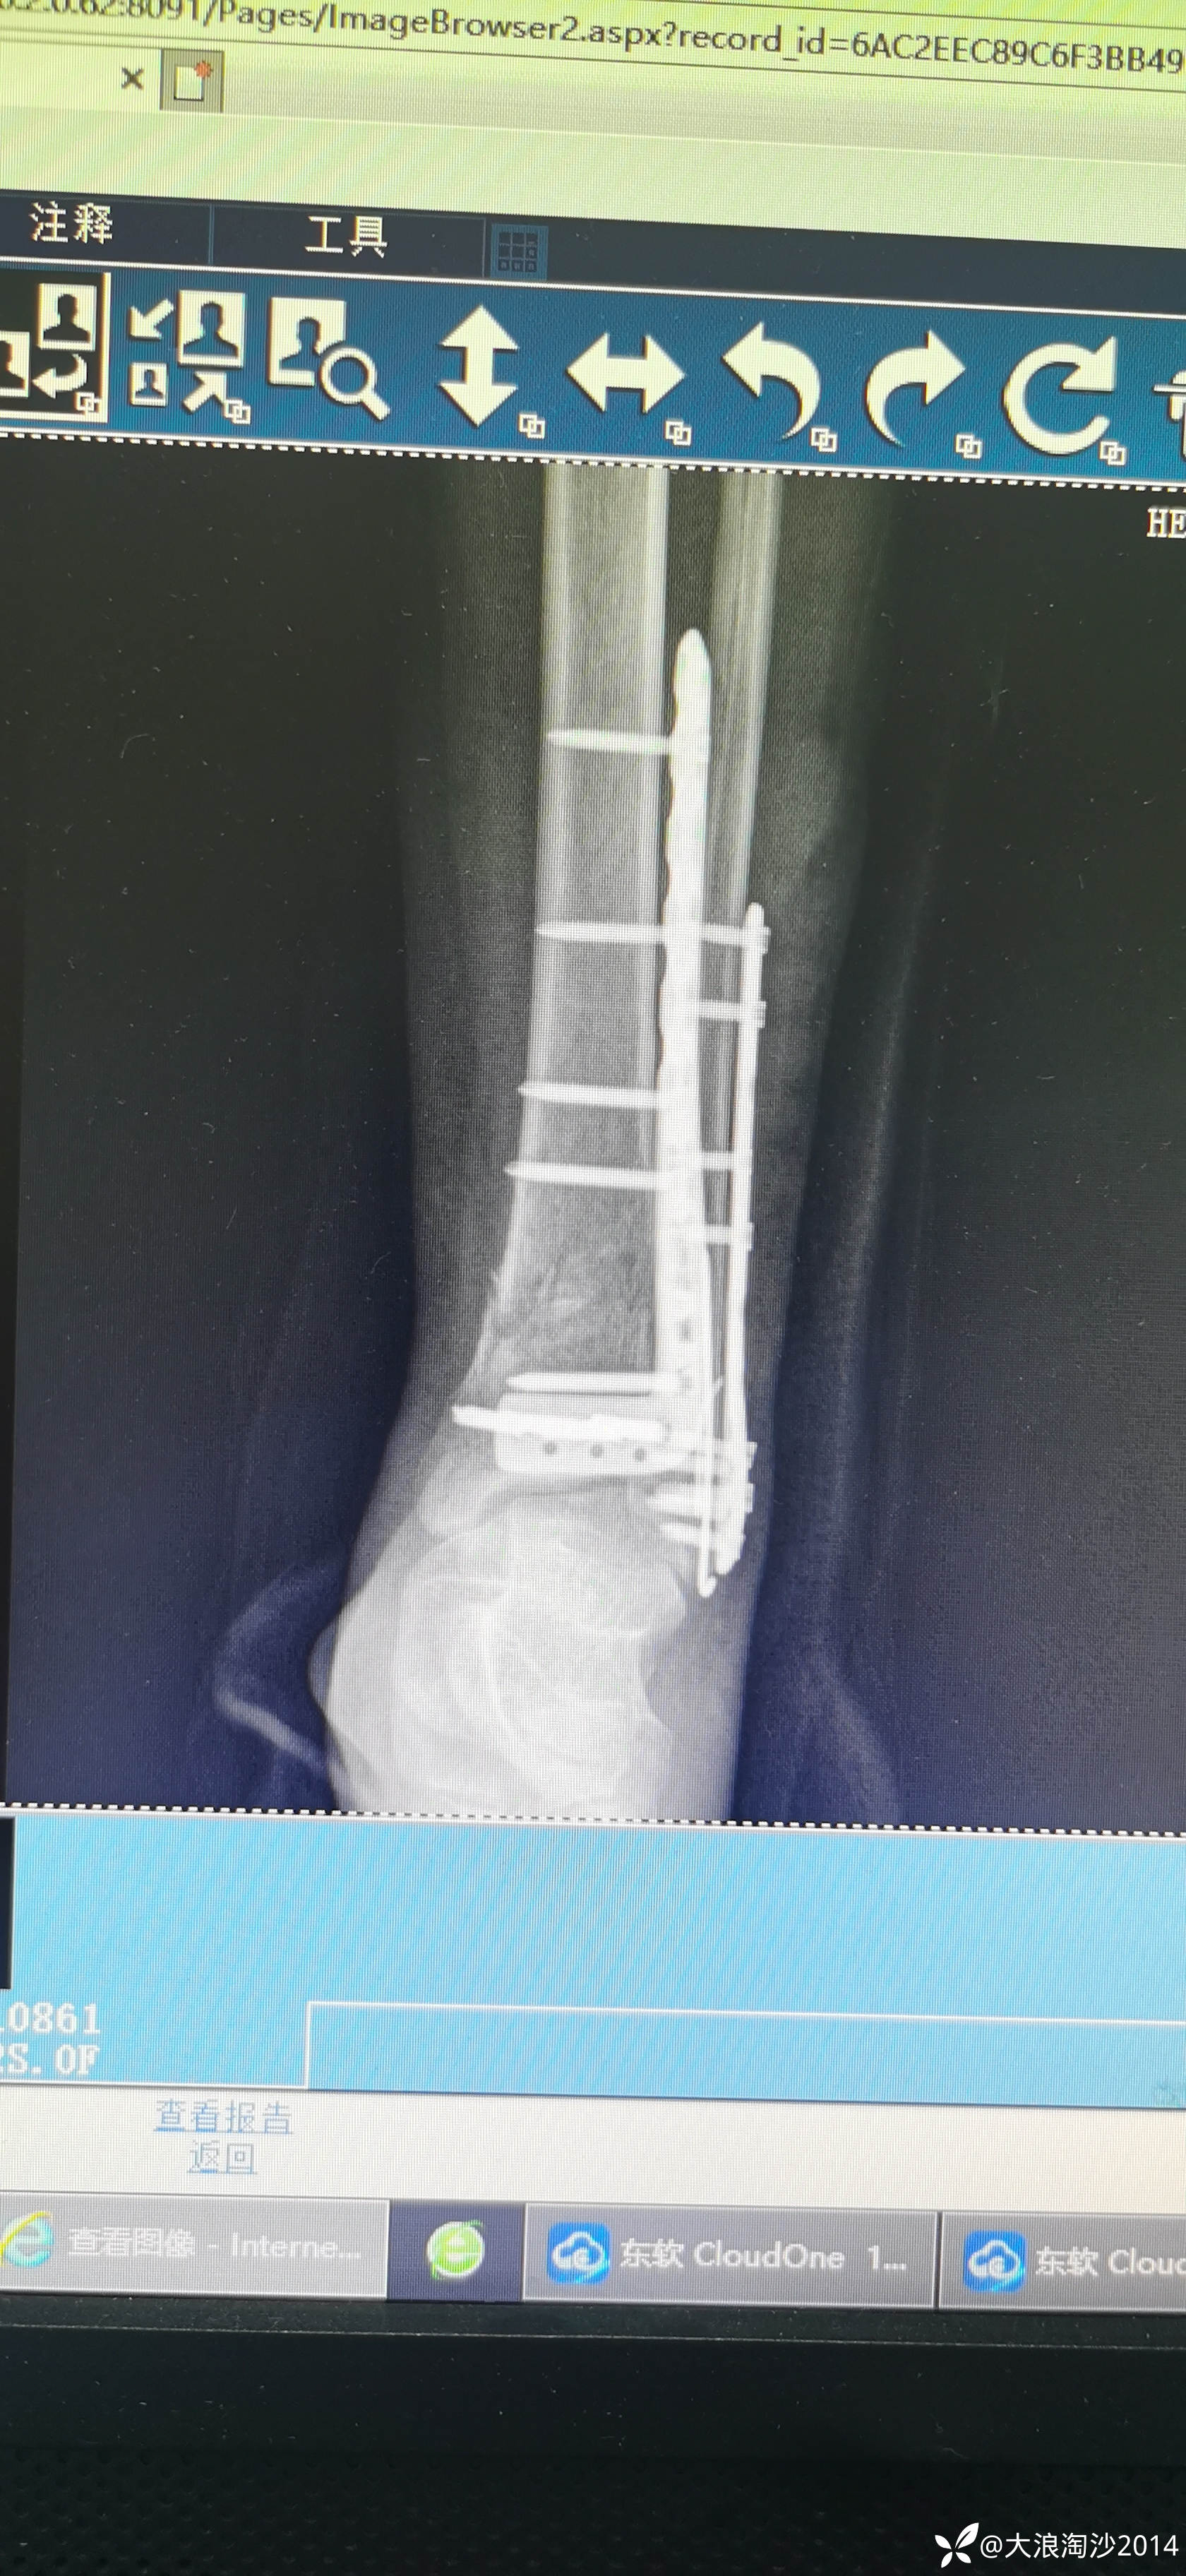

一65岁女性患者,偏瘦,体重75斤,车祸外伤致左胫腓骨远端骨折,入院后消肿后,病人可以用皮包骨头形容,考虑胫骨远折端不适合用内侧插板(mippo技术),病人太瘦,如取两个切口分别处理胫腓骨,切口容易出现问题,因此采用前外侧一个切口处理胫腓骨远端骨折(片子顺序上传有点乱)